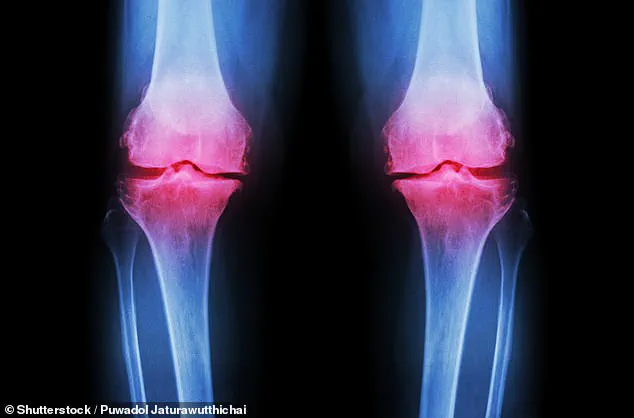

Once torn, cartilage does not heal on its own, leading to chronic pain, swelling, and eventual bone-on-bone contact.

This degeneration can severely alter joint structure, causing misalignment and long-term mobility issues.

Osteoarthritis, the most common form of arthritis, occurs when the cartilage that cushions the ends of bones wears down over time.

This breakdown leads to pain, stiffness, and reduced mobility, significantly impacting quality of life.

Articular cartilage, the smooth, rubbery tissue that cushions joints such as the hip, knee, shoulder, and ankle, has long been a medical enigma.

Unlike other tissues in the body, cartilage possesses minimal regenerative capacity once damaged, whether from injury or the natural wear of aging.

ACL tears can cause the cartilage to wear down, resulting in painful bone-on-bone friction within the joint.